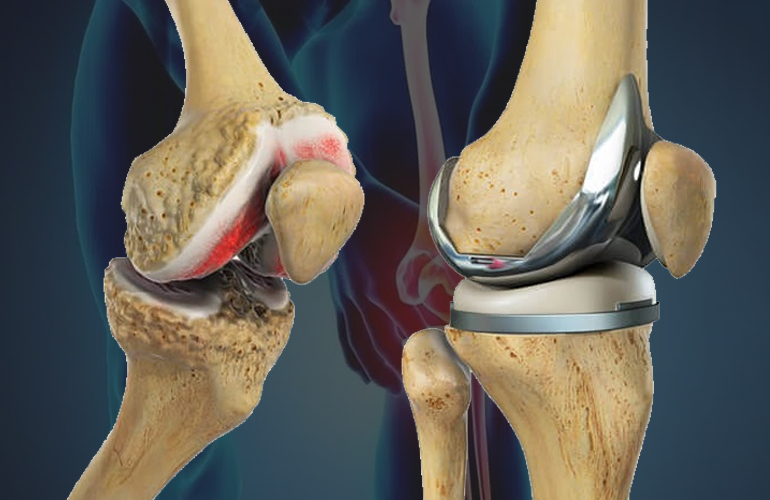

Joint replacement

I specialize exclusively in comprehensive hip care, encompassing the full spectrum of non-surgical and surgical treatments.

Knee Orthopedic

I specialize exclusively in comprehensive hip care, encompassing the full spectrum of non-surgical and surgical treatments.